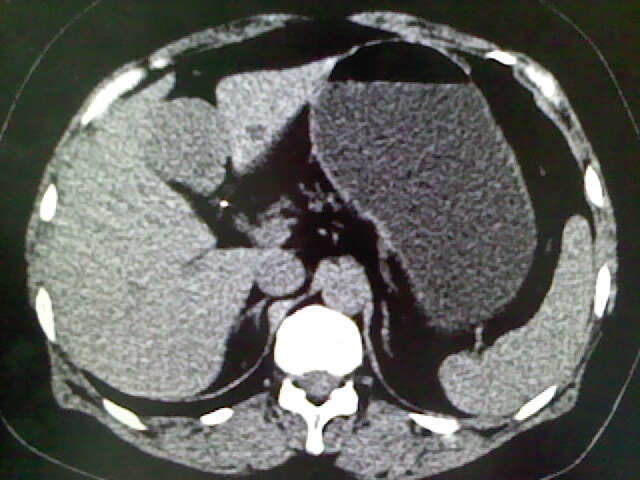

以下是引用卜一在2009-4-2 13:26:00的发言:[br]胆囊颈部结石伴胆囊炎!另:建议增强,待除外肝内占位及胆囊占位!

以下是引用liaoqiang在2009-4-2 16:23:00的发言:[br]胆囊是否切除?胆囊颈区致密影考虑金属夹?结石?肝脏右叶低密度影,考虑增强。